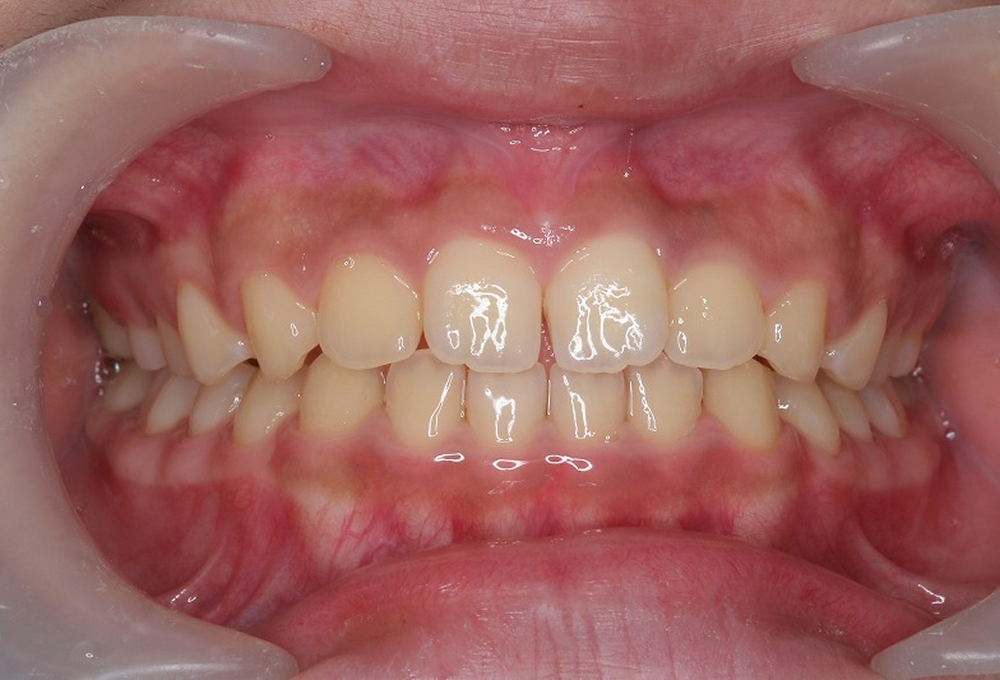

③術後